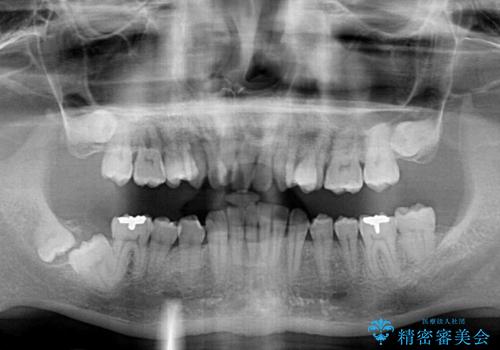

- ぶつけて前歯が折れてしまったとのことで来院された患者様です。

折れてしまった前歯は軽傷であり、歯内の歯髄に影響は及んでいませんでした。

通常では速やかにオールセラミッククラウンにて補綴治療を行うのですが、デコボコしている歯列も気になっていたため、事前に矯正治療を行うこととしました。

上顎歯列の叢生が著しかったため、上顎左右第一小臼歯2本を抜歯し、目立たないワイヤー装置にて治療を進めることとしました。